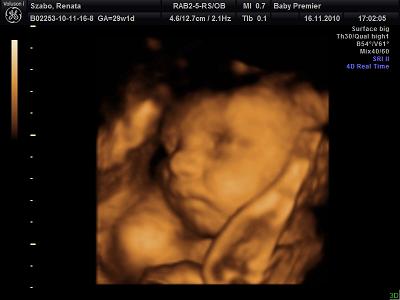

Köszönöm szépen a dícséretet. Igen én is beleszerettem a fülébe meg nekem a nózija az ami nagyon tetszik

Itt mutatja hogy minden rendben mami!A lábacskája is látszik.

Ez meg a szép mosoly,profilból!